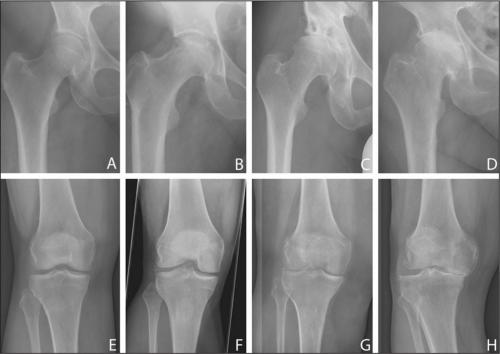

Все медикаментозные средства эффективны лишь на I—II стадиях артроза, но бессильны на III и IV. Если в патологию вовлечены не только суставы, но и кости, никакой препарат не поможет. В этом случае избавиться от хронических болей в суставах, трудностей при ходьбе, ограниченной подвижности суставов и других неприятных симптомов можно только с помощью операции.